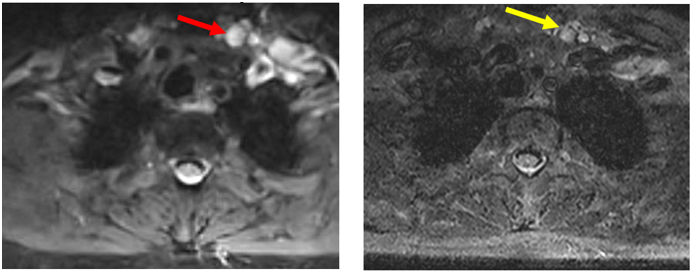

3.     Biến đổi trên chẩn đoán hình ảnh (trước và sau điều trị)

Hình ảnh MRI cổ: Hình ảnh tổn thương vùng hạ họng thanh quản giảm kích thước sau điều trị 3 tháng, từ 41 x 22mm (mũi tên đỏ) xuống còn kích thước 20 x 13mm (mũi tên xanh).

Hình ảnh MRI cổ: Hình hạch thượng đòn trái giảm kích thước sau 3 tháng điều trị, từ đường kính 10 mm (mũi tên đỏ) xuống còn 7mm (mũi tên vàng).

-         Sau 3 tháng, khối u hạ họng - thanh quản giảm kích thước còn 20 x 13mm, bệnh nhân cải thiện triệu chứng lâm sàng.